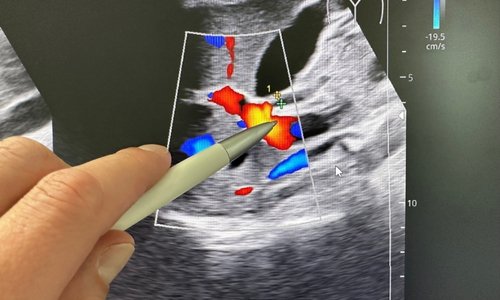

At Vcare Imaging & Diagnostic Center, Kandivali East, we provide high-resolution 3D and 4D sonography scans for pregnancy and diagnostic purposes. Our modern ultrasound technology delivers clear, real-time imaging, allowing expecting parents to see detailed images of the baby while enabling doctors to monitor fetal health accurately.

- Gynecological Ultrasound: Evaluate uterus, ovaries, and other pelvic organs.